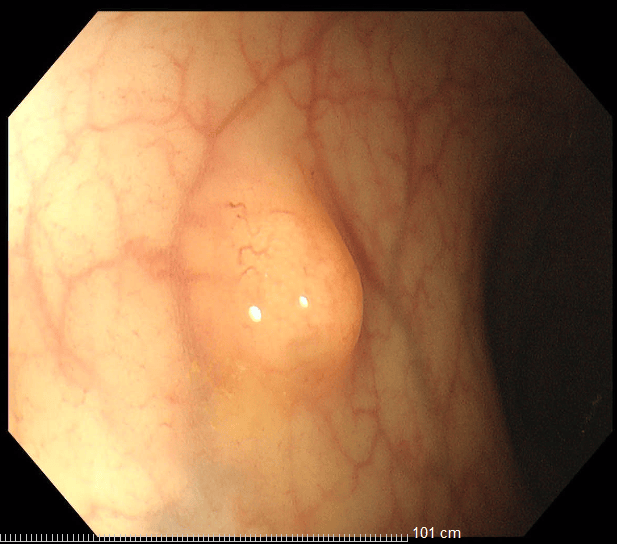

36歲的王先生在蘇州高新區人民醫院行胃腸鏡檢查時,發現直腸裡有1個息肉和2個黏膜下半球型隆起,表面光滑、顏色發黃,大小直徑約1.0cm,當時便做了超聲內鏡檢查,顯示2個隆起的腫物位於直腸黏膜下層,可能是神經內分泌腫瘤,1個粘膜層隆起的息肉可能是腺瘤腫瘤。消化科團隊立即為王先生進行了腸鏡下黏膜剝離術切除了2個粘膜下腫物,同時進行了腸鏡下粘膜切除術解決了1個腺瘤樣息肉,術後病理顯示:2個是神經內分泌瘤NET G1,切緣乾淨。1個管狀腺瘤伴低階別上皮內瘤變(屬於癌前病變),目前王先生恢復良好,已順利出院。

消化內科莊劍波主任介紹:神經內分泌腫瘤是一組起源於肽能神經元和神經內分泌細胞的異質性腫瘤,表現為從緩慢生長的低速惡性到高轉移性等明顯惡性的多樣性腫瘤。消化道是神經內分泌瘤最常見的發病部位,其中直腸起源的神經內分泌瘤佔比高達17.2%。